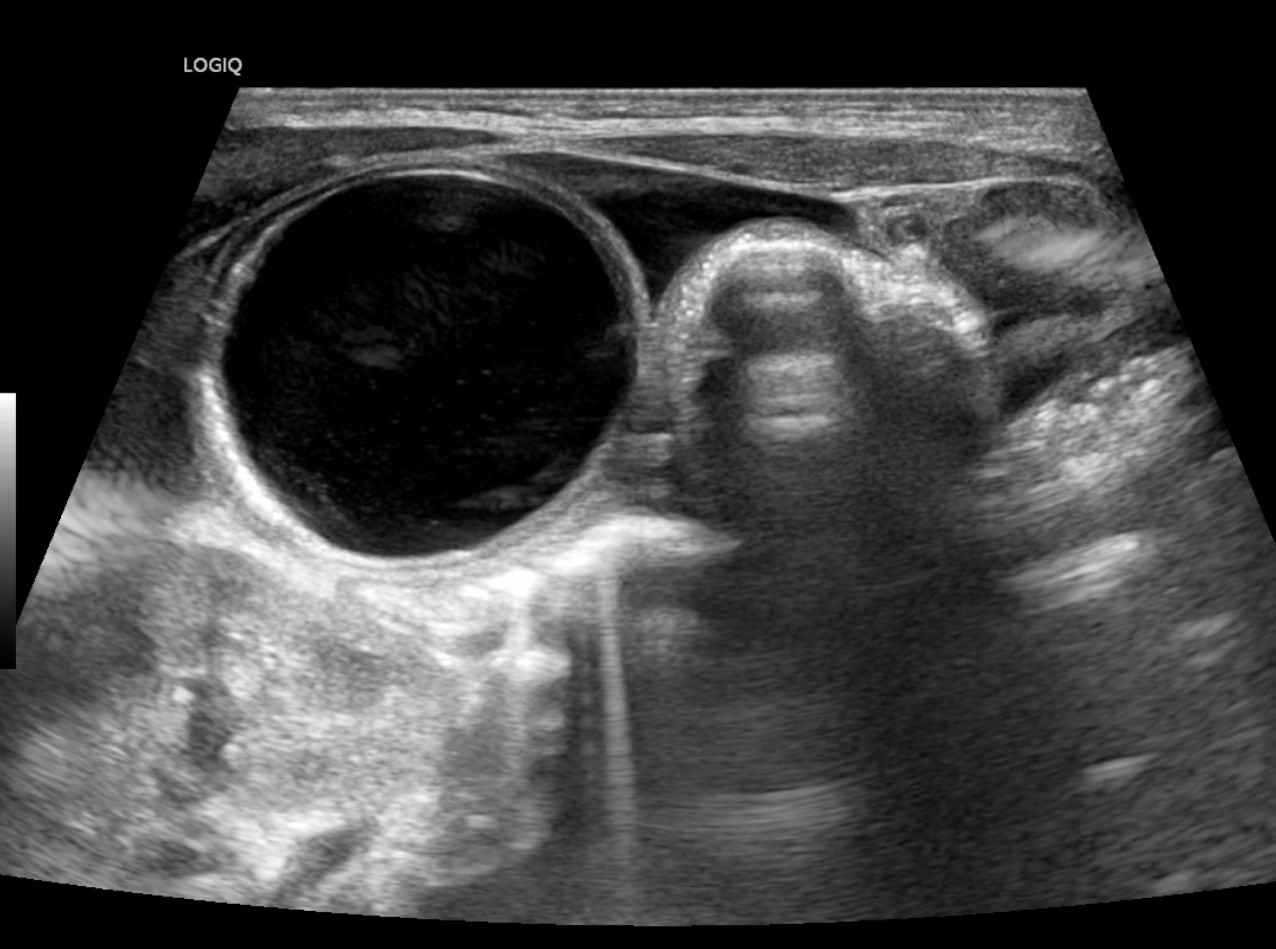

[359,Pediatric [Ped]] 1/F,Abdominal cyst was detected on prenatal ultrasound.

[Questions]  What's the diagnosis?

[Diagnosis]